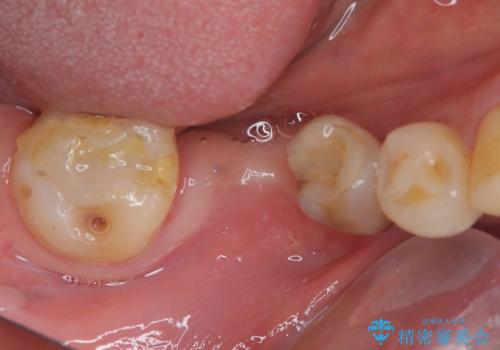

奥歯には治療途中で放置された歯があったため、矯正治療前に仮歯を装着し、矯正治療後にオールセラミッククラウンにて補綴治療を行うこととしました。

奥歯のむし歯、骨格の左右のずれや矮小歯、骨格的に上顎が前方にあるなど、治療を難しくする要素が多くあったため、期間はかかりましたが、非常にスッキリとした横顔の印象を達成することができました。